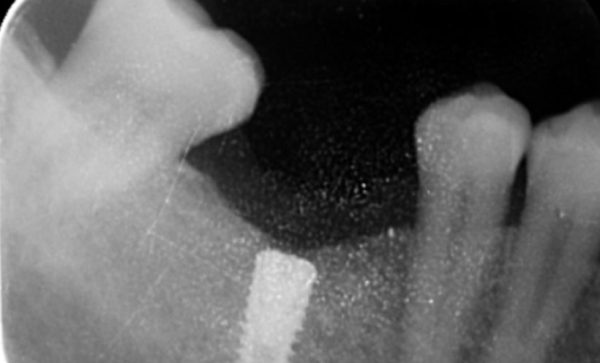

Case 32